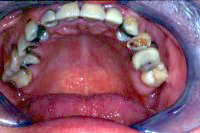

Und schliesslich geht es in der Zahnprophylaxe immer auch darum, den Zustand nach einer Zahnsanierung durch entsprechende individuelle Informationen und Instruktionen gesund zu erhalten wie das in den Abb. 2 und 3 gezeigt wird.